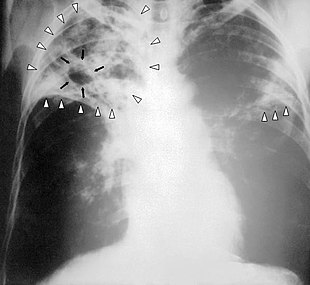

7. Other - Any other finding suggestive of active TB, such as miliary TB. Miliary findings are nodules of millet size (1 to 2 millimeters) distributed throughout the parenchyma.